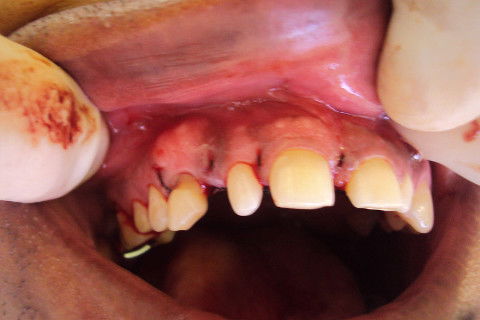

incisão

descolamento

esposição do descolamento

Ostectomia expondo o elemento dental

Odontossecção

Área após remoção dental

Acomodando tecido mocuperiostal

Tecido após acomodado

Sutura

Paciente V.S.D compareceu à Clínica Odontológica do ITPAC encaminhado pelo ortodontista para remoção do elemento nº 13 incluso em posição retroalveolar. Foi feito anamnese e exame radiográfico, posteriormente foi feito anti-sepsia extra com solução de P.V.P.I e intra oral com solução de digluconato de clorexidina a 0,12%, anestesia terminal infiltrativa por vestibular e palatina na região do elemento a ser extraído, interpapilar do elemento 16 ao 23, bloqueio dos nervos nasopalatino e palatino maior, incisão intrapapilar e descolamento até linha média. Ostectomia e odontossecção com broca esférica 1014 e carbaide 702 de haste longa, exodontia do elemento, curetagem, regularização óssea, irrigação com soro fisiológico, sutura, toalete do paciente e orientações pós-operatória.